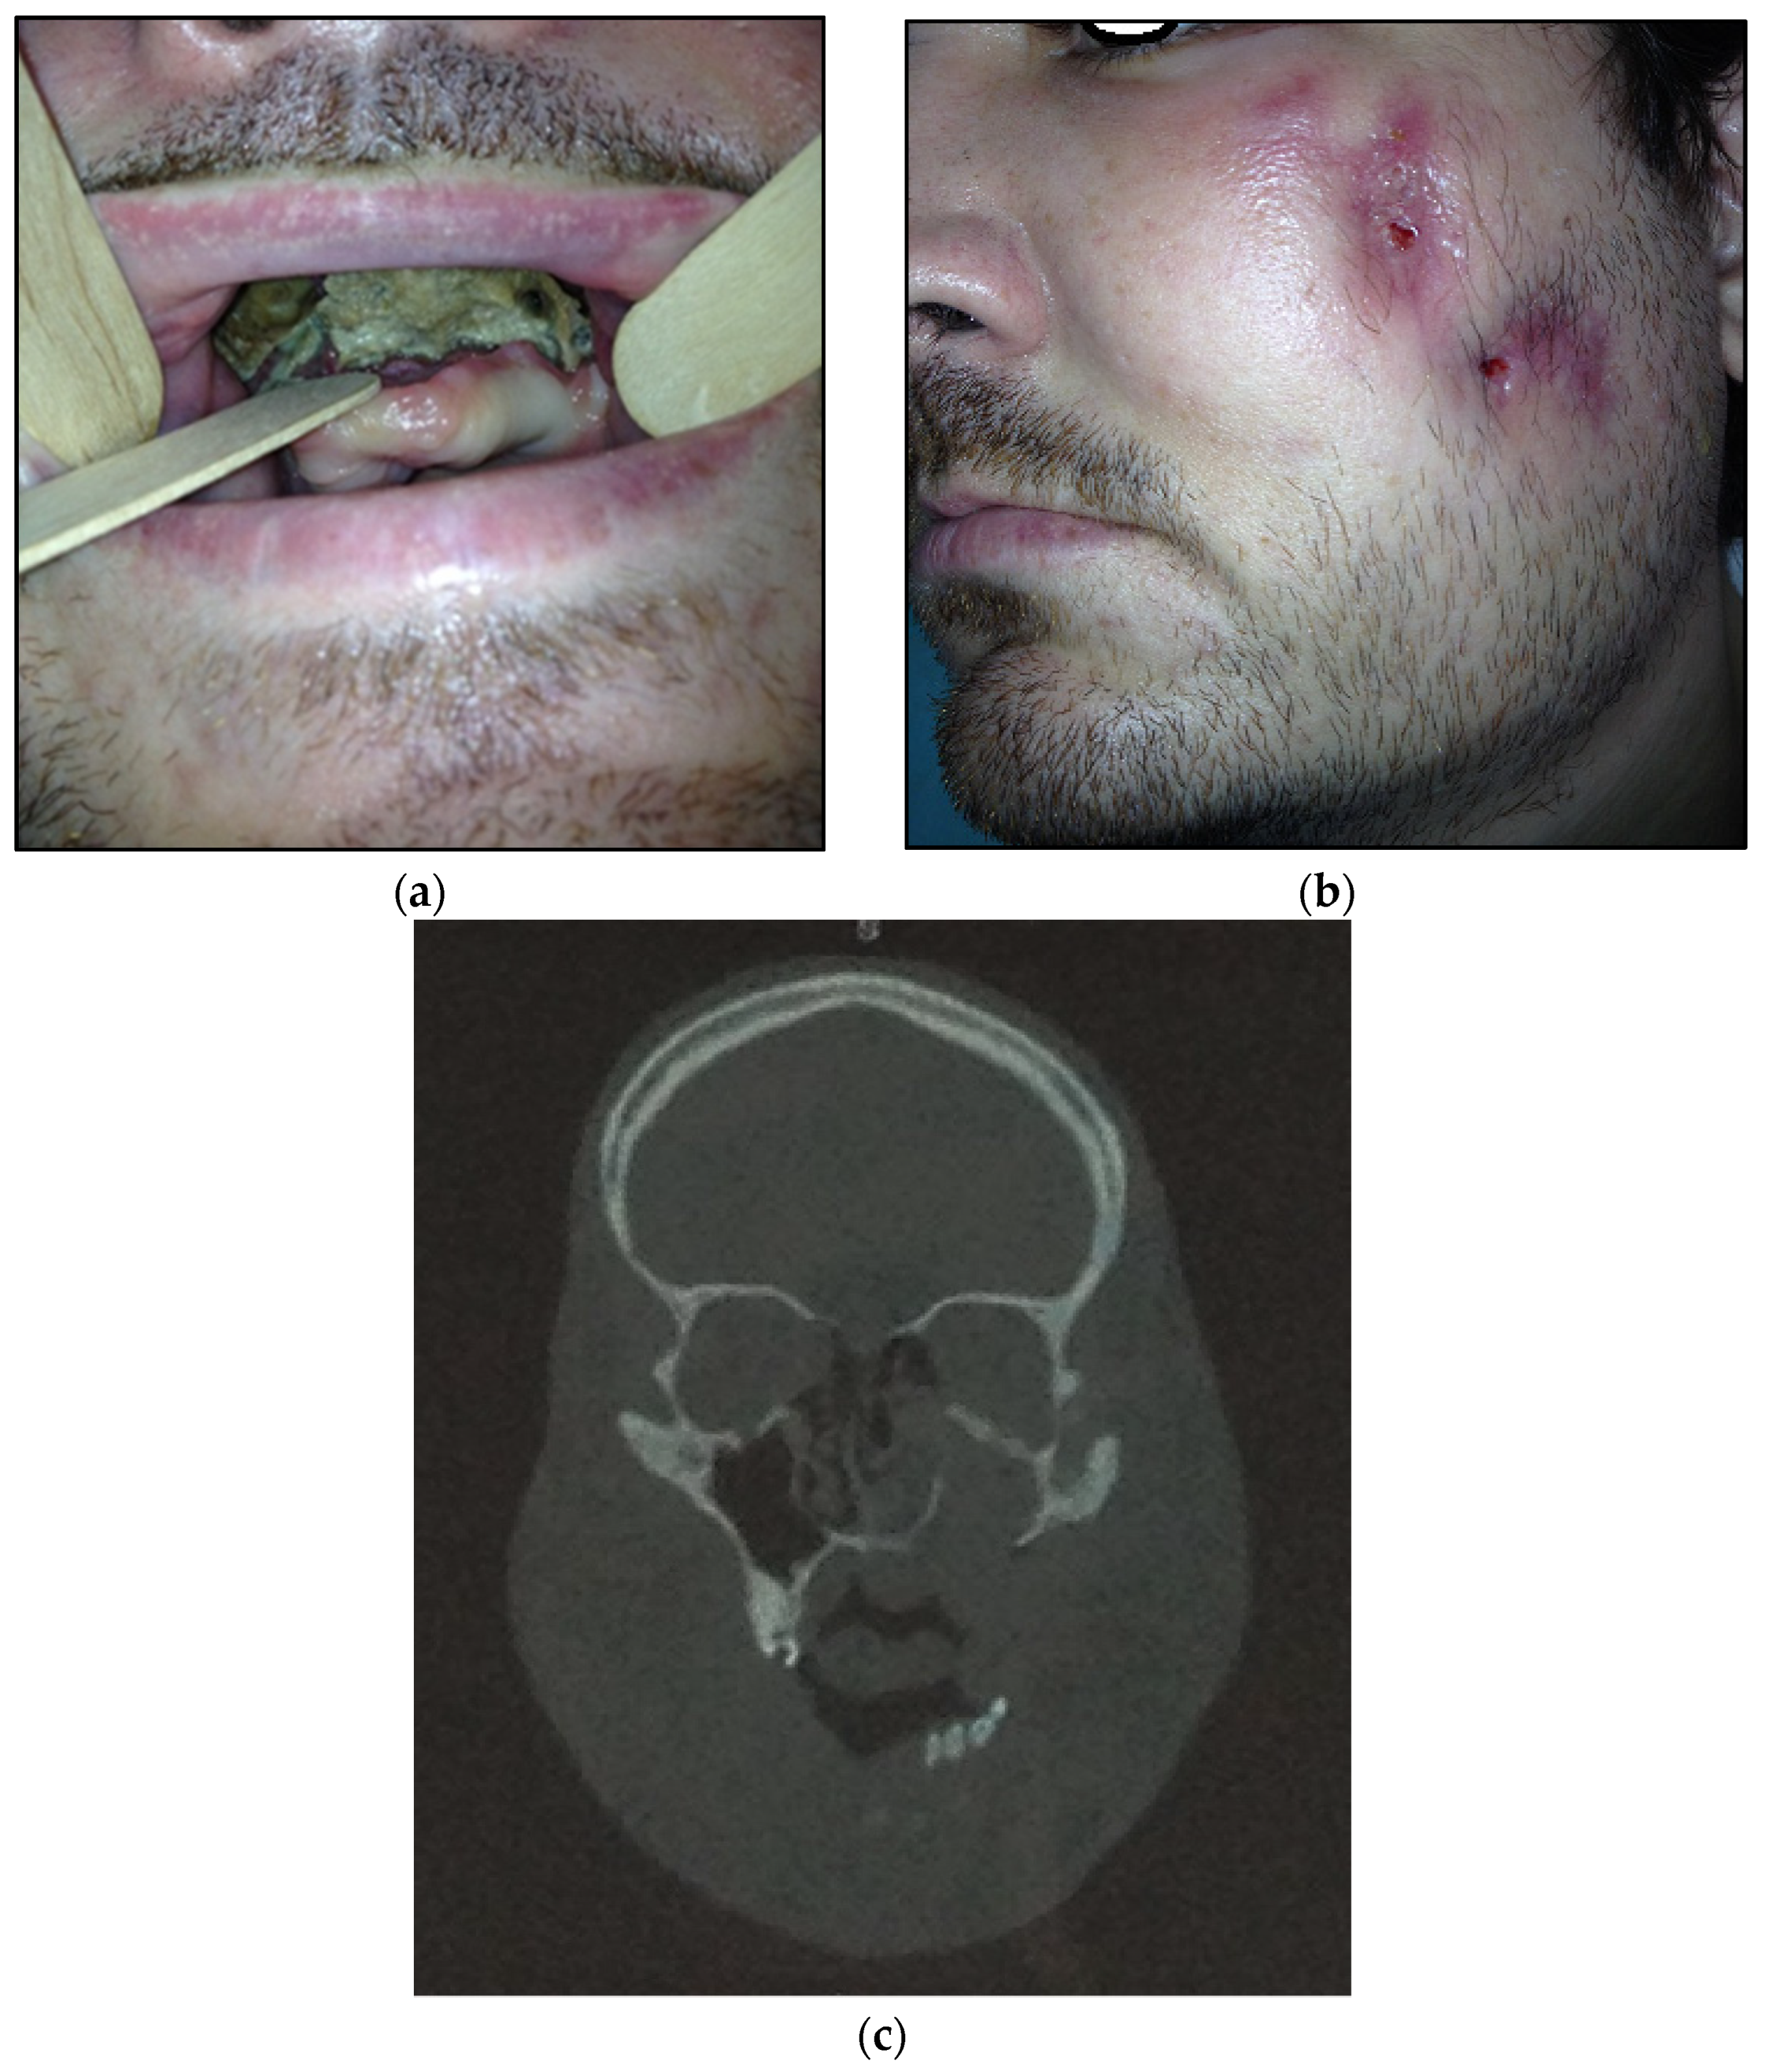

- Type 3: patients with maxilla and partially zygomatic bone (its body) involved—11 patients (22%) (Figure 3a–c);Figure 3. (a) Patient with type 3 toxic phosphorus osteonecrosis. Intraoral view; (b) extraoral view, (c) multi CT-scan of patient’s skull before operation.Figure 3. (a) Patient with type 3 toxic phosphorus osteonecrosis. Intraoral view; (b) extraoral view, (c) multi CT-scan of patient’s skull before operation.